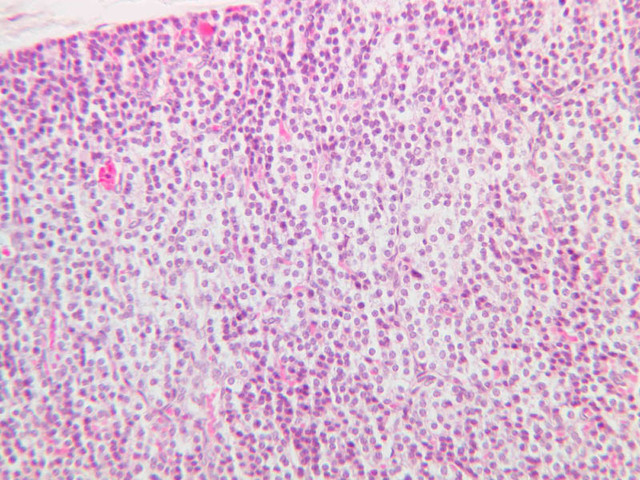

Examine slide B-56 (H&E [2.5x, 10x, 20x, 40x-labeled] [10x, 20x, 40x-labeled] [20x, 40x] [10x, 20x, 40x-labeled] [10x, 20x, 40x]). The connective tissue capsule of each parathyroid gland is continuous with that of the thyroid gland. It extends into the substance of the gland, dividing it into poorly defined lobules. Fat cells may separate the groups of cells and increase with age. Note the rich capillary network. The parenchyma is composed of two types of cells: (1) Principal or chief cells and (2) oxyphil cells. The polygonal chief cell is by far the more numerous cell type. Its nucleus is centrally located and has a vesicular chromatin pattern with a prominent nucleolus and its cytoplasm stains rather lightly. Oxyphil cells, which are less regular in shape and considerably larger than chief cells, are scattered singly or in small clusters. Their nuclei are smaller and more condensed than those of the chief cells and, owing to a very rich complement of mitochondria, their cytoplasm is distinctly acidophilic.